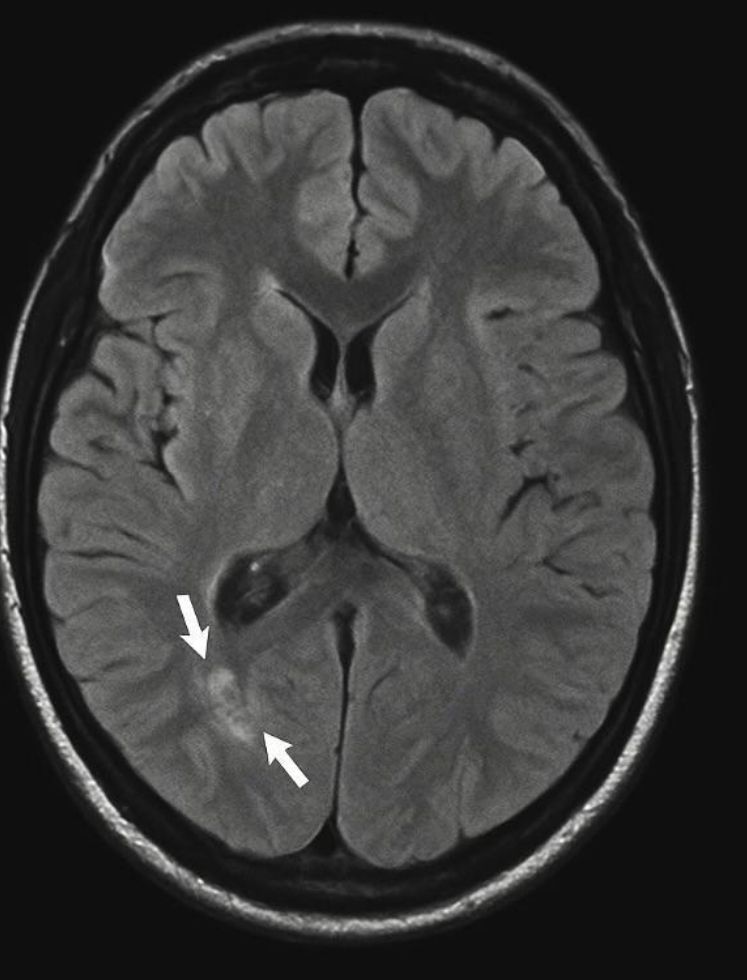

We report a 24-year-old female presenting with acute psychosis, behavioral changes, and insomnia, initially treated as a primary psychiatric disorder. She later developed seizures, orofacial dyskinesia, and autonomic dysfunction. CSF analysis revealed strongly positive anti-NMDA receptor antibodies, and pelvic imaging identified a left ovarian teratoma. The tumor was surgically removed and followed by immunotherapy with corticosteroids and IVIG. She achieved complete recovery within six months.